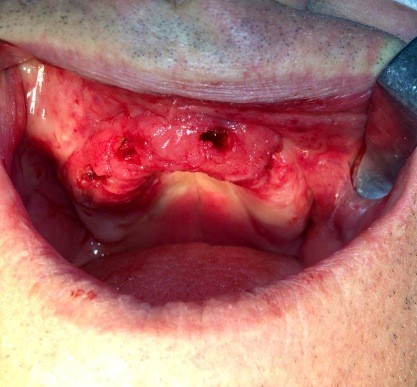

rigenerazione grave difetto parodontale a carico una intera emiarcata